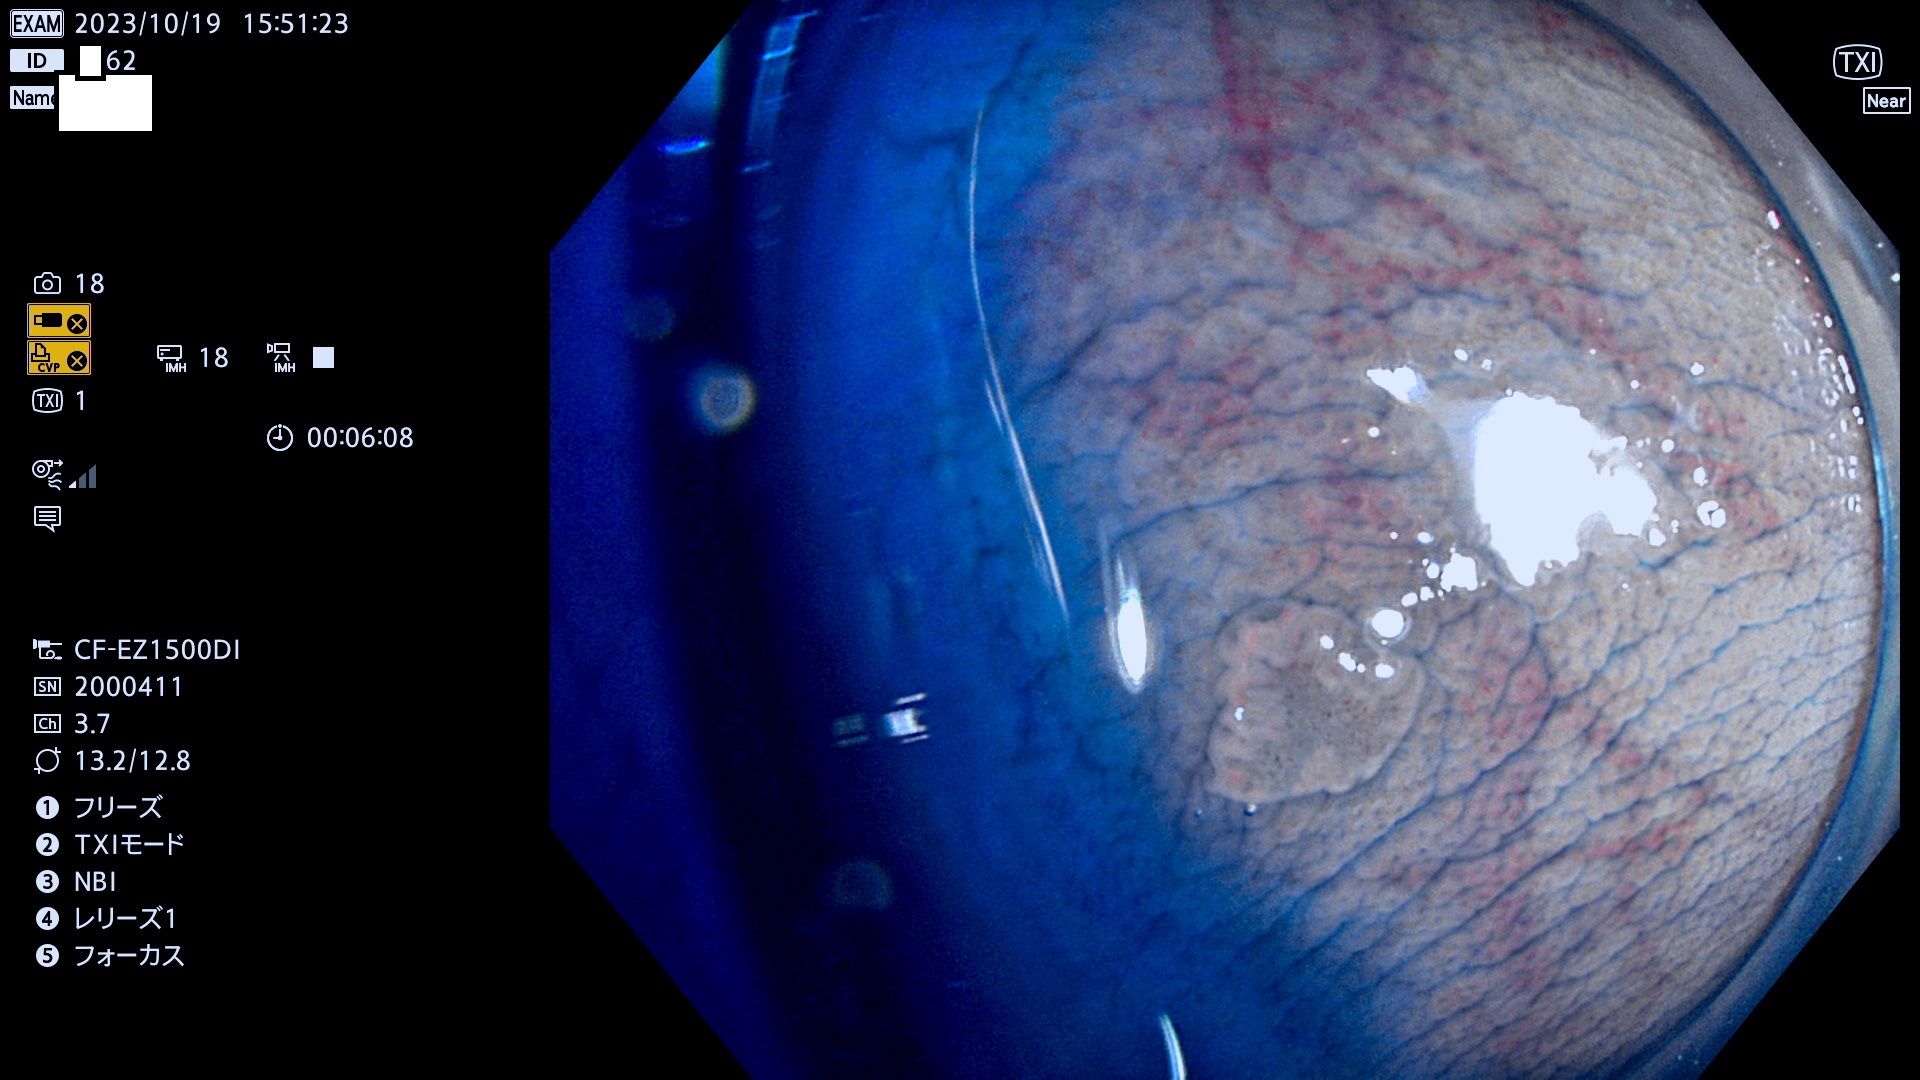

抽出の対象期間 2023年10月19日(木)〜10月22(日)の4日間(48件の検査)5件

炎症(ビラン)と鑑別の困難なUc型腺腫の例